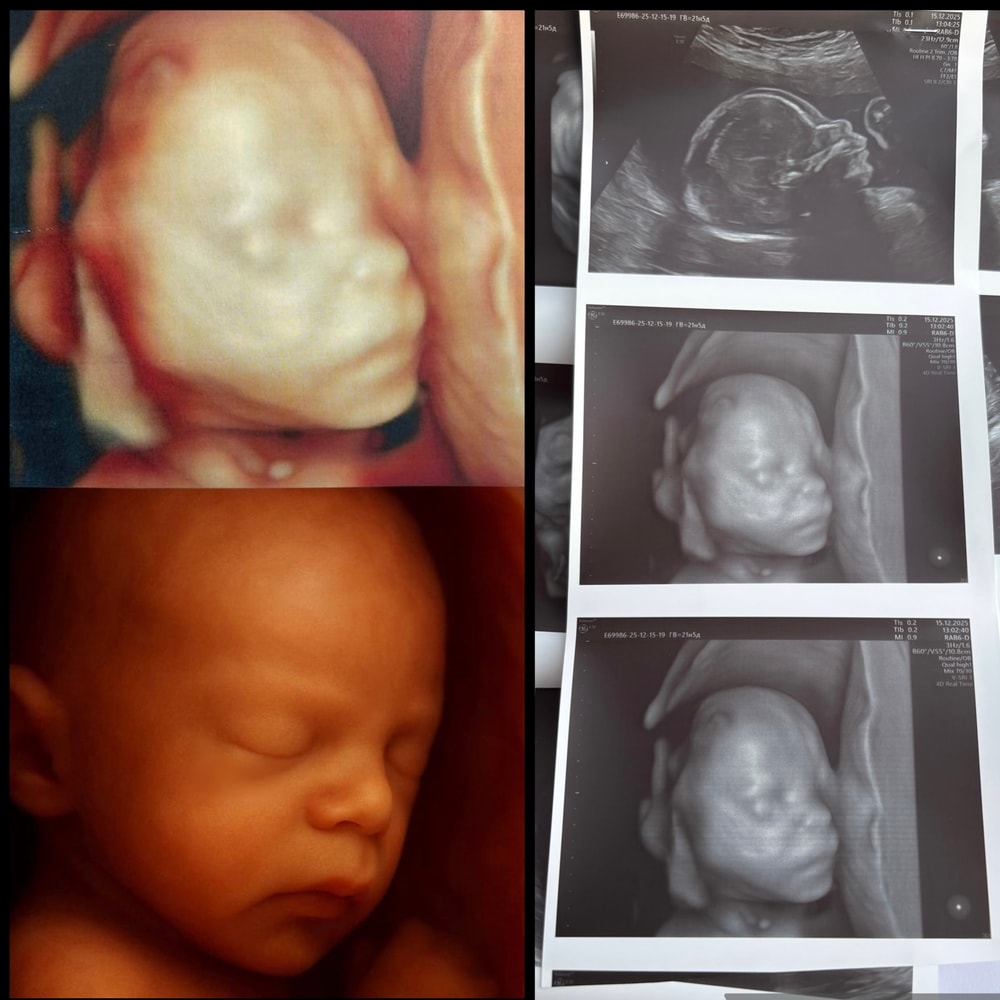

Сходили перед отпуском к Пятых. Посмотреть кровоток, т к у пуповины единичная артерия (ЕАП), еще раз сердечко, которое уже подросло и шейку.

21н 5 д. По размерам сын на 22-23 нед